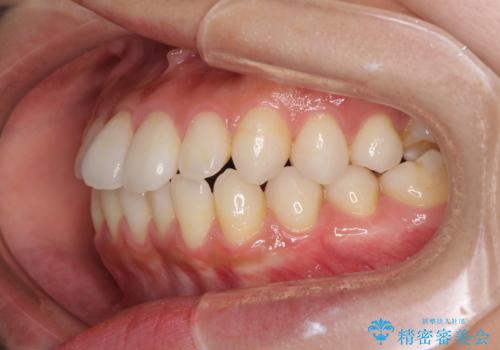

インビザラインで口を閉じやすく

- 下唇に上の前歯が当たることを気にして来院された患者様です。

上顎の親知らずを抜去し、歯列全体を後方に移動させるとともに、IPR(歯と歯の間を削る)を行うことで口元の閉じにくさを改善していくこととしました。

咬合力が強く、マウスピースを介した咬み込みが顕著であったため、奥歯の咬みにくさやIPRのスペースが改善しにくく、治療期間が思った以上にかかってしまいました。